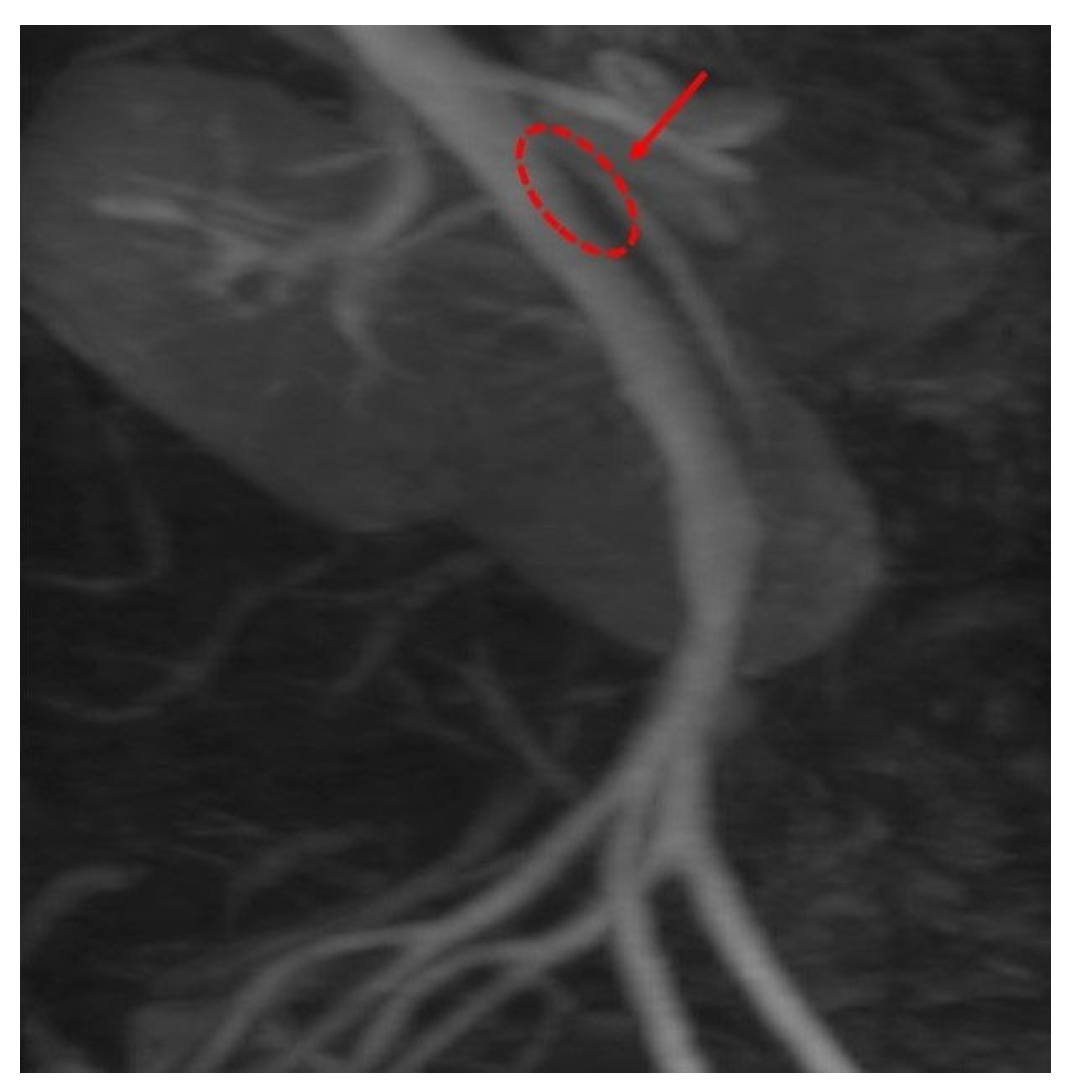

Computed Tomography Angiography (CTA) Figure 2, provided definitive anatomical correlation. At the level where the third portion of the duodenum crosses between the abdominal aorta and the SMA, the aortomesenteric angle was significantly reduced to 6° (normal: 38–56°), Figure 3 and the aortomesenteric distance measured 4 mm (normal: >10 mm, with <8 mm considered pathological). Figure 4 These findings were consistent with SMAS, a rare condition caused by vascular compression of the third portion of the duodenum between the SMA and the aorta.

Figure 2. CTA: The aortomesenteric angle was significantly reduced to 6°.

Figure 3. CTA: The aortomesenteric distance measured 4 mm.